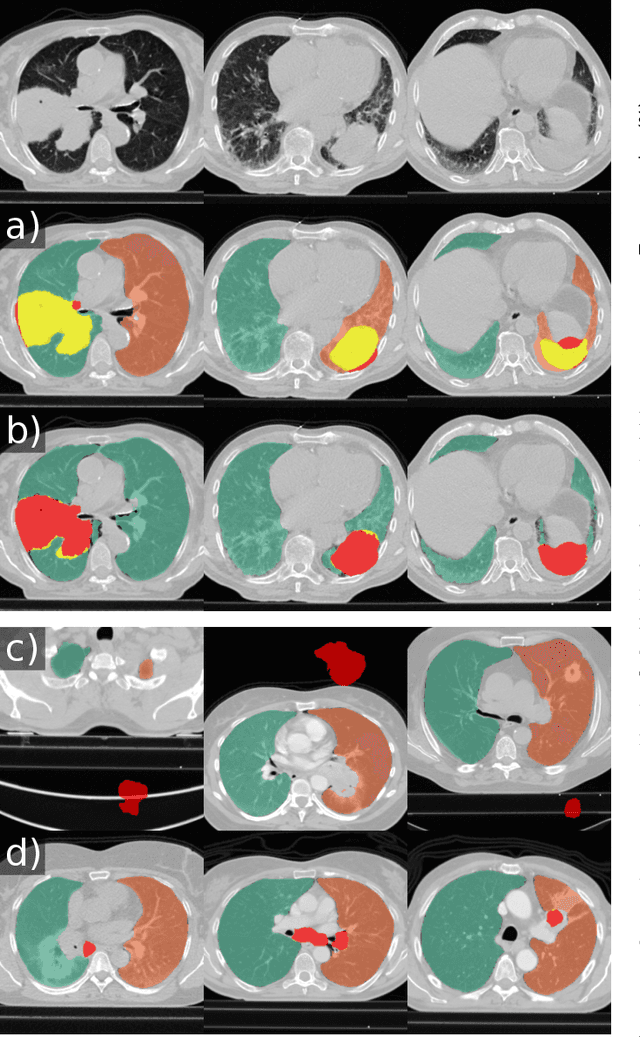

Abstract:Automated segmentation of anatomical structures is a crucial step in many medical image analysis tasks. For lung segmentation, a variety of approaches exist, involving sophisticated pipelines trained and validated on a range of different data sets. However, during translation to clinical routine the applicability of these approaches across diseases remains limited. Here, we show that the accuracy and reliability of lung segmentation algorithms on demanding cases primarily does not depend on methodology, but on the diversity of training data. We compare 4 generic deep learning approaches and 2 published lung segmentation algorithms on routine imaging data with more than 6 different disease patterns and 3 published data sets. We show that a basic approach - U-net - performs either better, or competitively with other approaches on both routine data and published data sets, and outperforms published approaches once trained on a diverse data set covering multiple diseases. Training data composition consistently has a bigger impact than algorithm choice on accuracy across test data sets. We carefully analyse the impact of data diversity, and the specifications of annotations on both training and validation sets to provide a reference for algorithms, training data, and annotation. Results on a seemingly well understood task of lung segmentation suggest the critical importance of training data diversity compared to model choice.